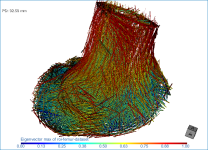

This section of the proximal femur tutorial describes how to compute high-resolution anisotropy maps in different orientations. You should note that when computing high-resolution maps, you should limit the volume of operation to regions that enclose only part of the region of interest. This can be done by creating a series of boxes that describe a particular orientation.

The images below (from left to right) correspond to XZ, XY, and oblique orientations. The computed vector fields are colored by magnitude.

High-definition vector field-based surface anisotropy maps